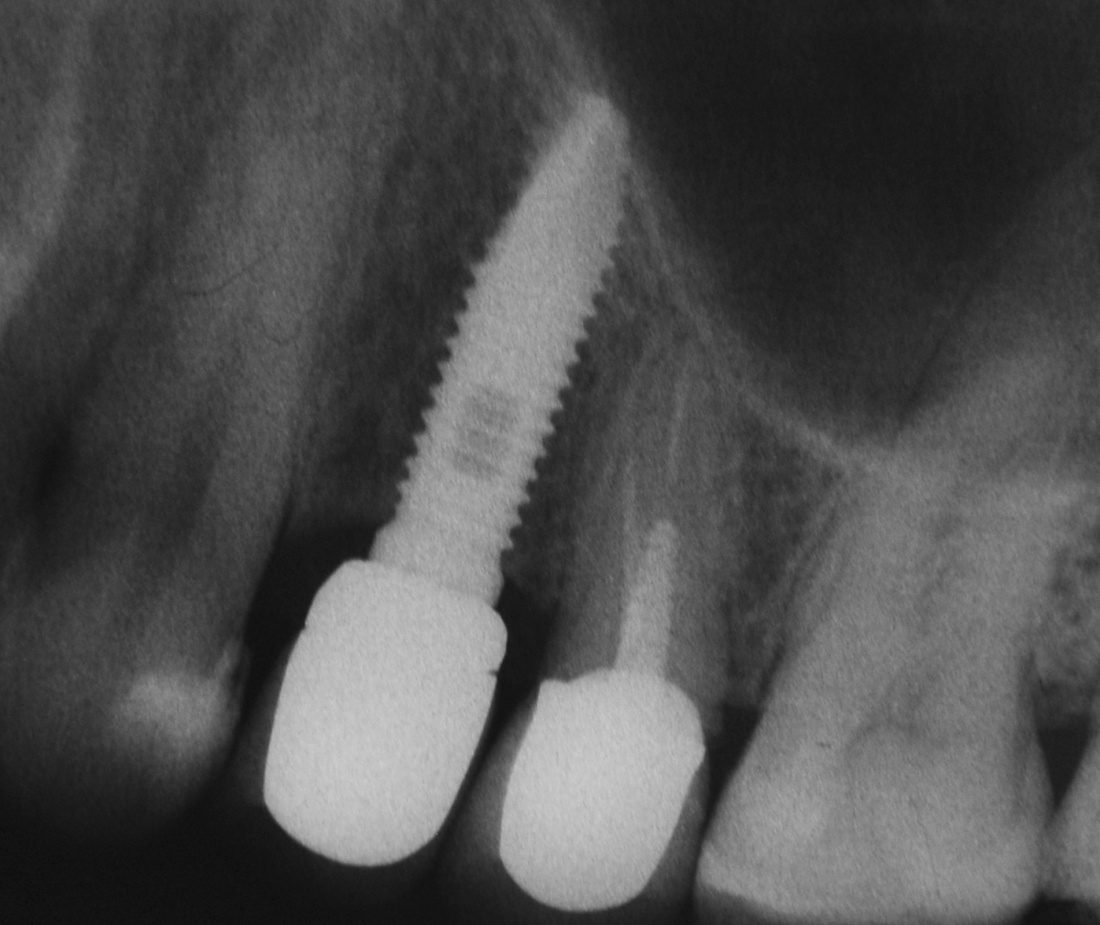

Кстати, обрати внимание на ширину альвеолярного гребня (левая картинка). Она чуть меньше 3 мм. Это объясняет, почему я засомневался в возможности установки имплантатов одновременно с остеопластикой. Понятно и без КЛКТ.

Возвращаемся к основной операционной области. Еще раз посмотрим на альвеолярный гребень, поофигеваем от его ширины и моих грандиозных планов:

Я зафиксировал костный блок практически без адаптации на несколько винтов. Обрати внимание, что винты находятся в зоне, где не планируется установка имплантатов. Фиксация должна быть надежной, поскольку мне еще предстояла подготовка лунок для имплантатов. Трех винтов для этого вполне достаточно.

Напомню, что для этой работы я выбрал субкрестальные имплантаты Ankylos C/X. Они прекрасно сочетаются с любым методом остеопластики.

Глянем на то, что получилось: